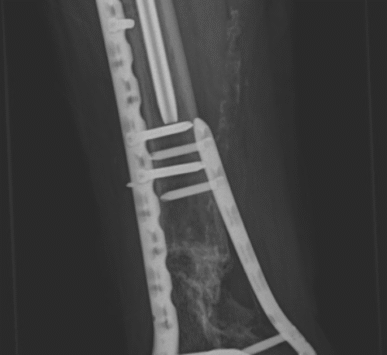

Entre sus áreas de especialización, se encuentran el tratamiento de fracturas complejas, la cirugía de pelvis y acetábulo mínimamente invasiva y la reconstrucción ósea con fijadores circulares para el tratamiento de pseudoartrosis e infecciones.

Ocurre cuando una fractura no sana correctamente o tarda más de lo esperado en curar.